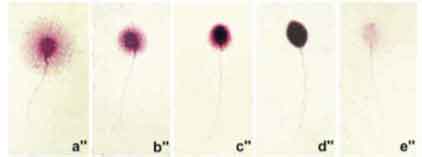

On distingue les spermatozoïdes avec un ADN fragmenté face à ceux qui gardent leur ADN intact. Les spermatozoïdes avec un ADN fragmenté ne développent pas un halo de dispersion ou bien celui-ci est minime.

L’intégrité de l’ADN est proportionnelle à la dispersion de la chromatine Il existe 5 classes, les classes a et b correspondent à un ADN Non fragmenté, les classes C et D à un ADN Fragmenté, la classe E à une absence d’ADN.